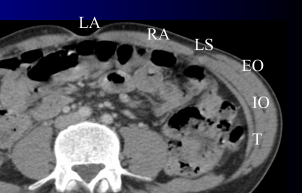

Anatomie

Ligne blanche (LA), Muscle droit (RA), Ligne semi-lunaire (LS), Obliques (Externe (EO), Interne (IO), Transverse (T))